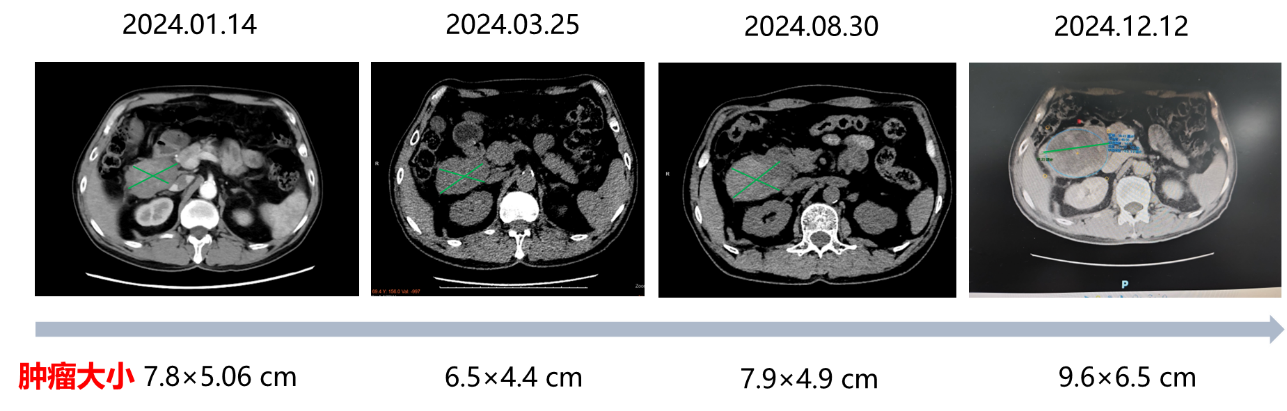

2024.03.25伊马替尼治疗约1个月,外院CT提示肿瘤大小由7.8cm×5.06cm缩小至6.5cm×4.4cm;

2024.08.30伊马替尼治疗约6个月,外院CT提示肿瘤增大至7.9cm×4.9cm;

2024.12.12伊马替尼治疗约10个月,我院CT提示肿瘤进一步增大至9.6cm×6.5cm,评效为疾病进展(PD)

服用伊马替尼400mg QD 10个月复查结果